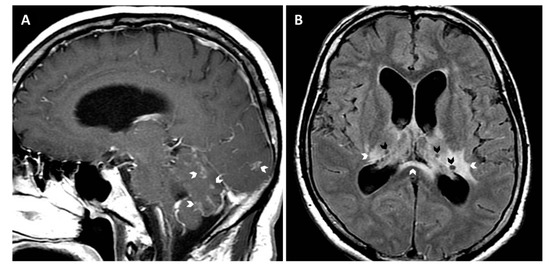

2. Case Report and Results